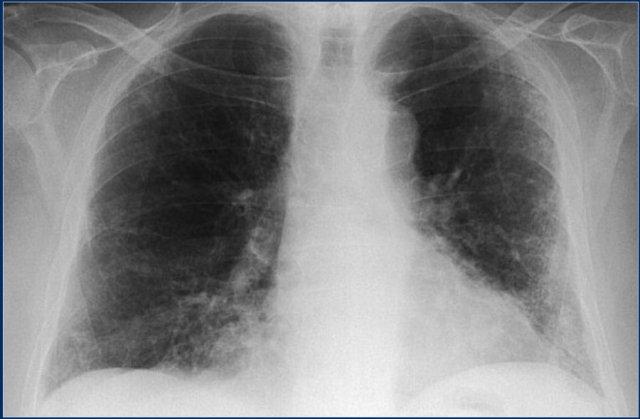

Mycobacteria không lao

Mycobacteria không lao, còn được gọi là mycobacteria không điển hình, là tất cả các loài mycobacteria khác có thể gây bệnh phổi giống lao.

Đây là hình ảnh bệnh nhân có bệnh hoạt động ở cả hai thùy trên do nhiễm mycobacterium không điển hình.

Lưu ý mức khí-dịch cho thấy có mủ trong hang (mũi tên).